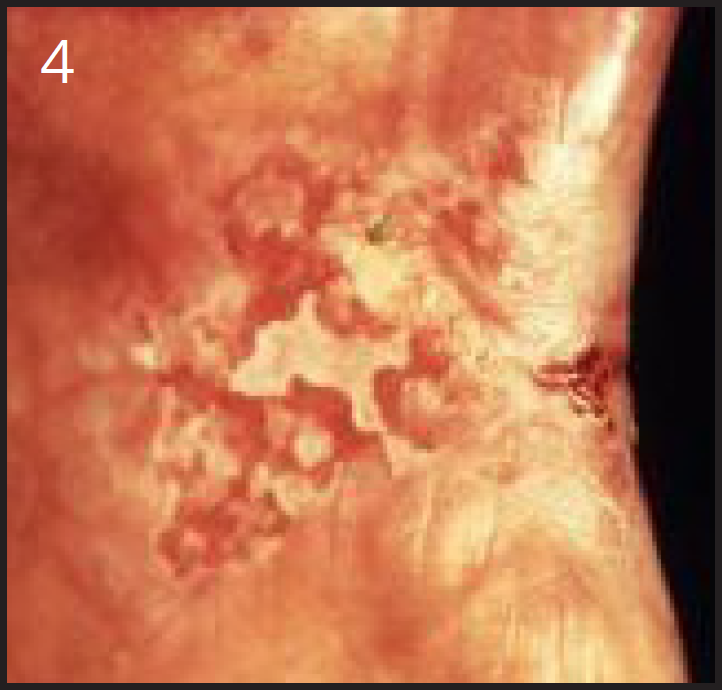

Epidermoid carcinoma (squamous cell carcinoma) is the most common oral cancer (Figure 3). Most typically seen in cigarette smokers, it is frequently found on the buccal mucosa or tongue. In addition, pipe smokers are more likely than other tobacco users to develop lip cancer. Erythroplakia, a red lesion, may also be associated with malignancy (Figure 4). Any red or white lesion, even those which are innocent looking, must have biopsies performed if they do not heal within a few weeks. Treatment of oral cancers may consist of surgery, radiation, chemotherapy or a combination of these approaches.21-23

Figure 4 – Erythroplakia, Used with Permission, www.docspiller.com

Figure 4

Erythroplakia - a particularly dangerous form of oral cancer which appears as a red, velvety-appearing patch.